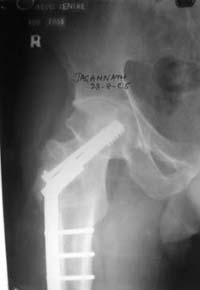

По моему, 120 градусная угловая пластина blade plate решит все проблемы, только необходим предварительный расчет угла остеотомии, и во время фиксации пластины не забыть латерализацию бедра, иначе ось конечности от варуса перейдёт в нежелательный вальгус.

Для предупреждения вальгуса клинок пластины берется на 10-12 мм длиннее чем предварительный туннель на головке, тогда во время

фиксации за бедро пластина автоматически приблизит бедро и происходит латерализация бедра. Если между клинком и латеральным кортексом бедра положить частицу кости от остеотомии тогда образуется дополнительная компрессия на фокусе несращения.

Здесь мои диаграммы для расчета угла остеотомии и латеризации бедра.